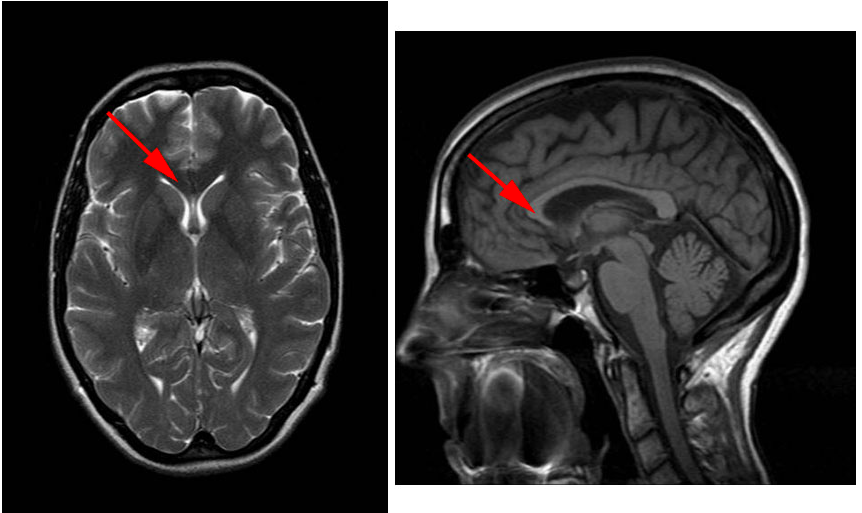

In these MRI (T1 weighted) images, the fibres making up the structure indicated by the red arrow are classified as:

Commissural